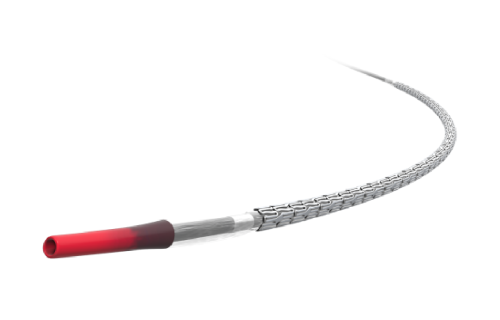

Em Cirurgia Vascular, Endovascular e Radiologia Intervencionista oferecemos uma ampla gama de soluções, incluindo enxertos endovasculares, cateteres de trombectomia e dispositivos de embolização. Esses produtos são vitais para o tratamento de doenças vasculares complexas, como aneurismas e tromboses, proporcionando aos profissionais de saúde as ferramentas necessárias para intervenções precisas e eficazes.

Nossa atuação em Neurorradiologia Intervencionista inclui a oferta de microcateteres e stents especializados para o tratamento de aneurismas cerebrais e outras condições neurológicas críticas. Esses dispositivos são desenvolvidos com tecnologia de ponta para garantir a máxima segurança e eficácia durante os procedimentos, ajudando a preservar a integridade cerebral dos pacientes.